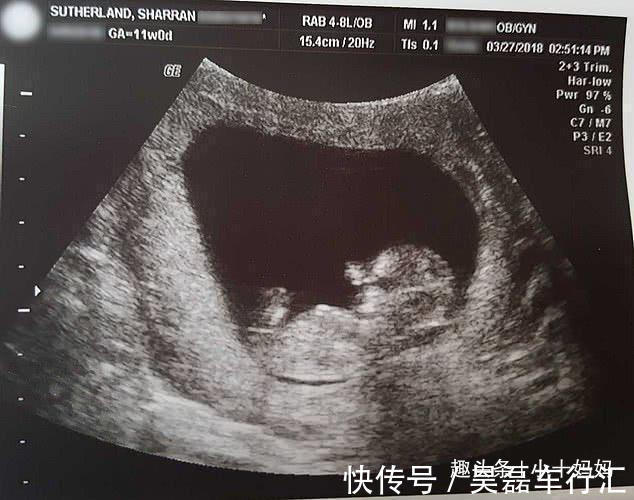

这位来自外国的女人本应该做一个快乐无比的妈妈,可是在怀孕14周的时候,医生的一句话让他顿时间抛弃了这样的想法。医生表示:很抱歉,你的孩子流产了。当听到这句话之后这位女人就像是疯了一样,他根本不相信医生说的话是真的。但是事实就摆在眼前,不相信也是没有办法的。因此医生希望他做刮宫手术,可是这位女子却拒绝了,因为她实在是不想看到自己的孩子被切成碎片。于是女子选择自然分娩,因为她从来都不觉得自己的孩子是医疗垃圾,所以女子还为宝宝取了一个名字叫米兰。

要知道14周的婴儿仅仅有了人的形状而已,但与正常的婴儿还是有着一定的差距的。不过这位女子并没有放弃死去的婴孩,而是选择把婴孩儿冷冻,为了防止婴儿腐烂,女子还特意将婴孩摄入了生理盐水,最后把婴孩儿放在了花盆里。女子每一年都能看到花盆在开花,女子曾表示能见到这一幕,也算是自己的幸运了。